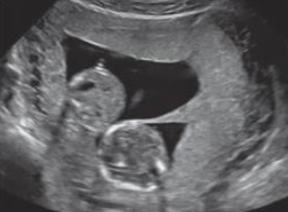

Considerando uma paciente do sexo feminino, 33 anos, com Beta HCG positivo, analise a seguinte imagem do ultrassom e assinale a alternativa correta.